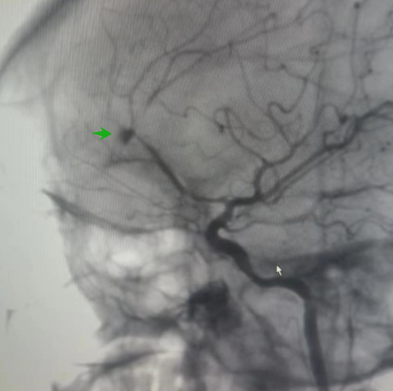

▲DSA下瘤体显影不完全

经神经外科介入手术团队充分知情告知、签字同意后,紧急启动治疗方案:全麻下实施脑血管造影及血管内治疗。脑血管造影(DSA)显示瘤体显影不完全,我们称之为“鬼影”或“幽灵”动脉瘤,是创伤性动脉瘤的显影特征,提示瘤体不稳定、易破裂出血。